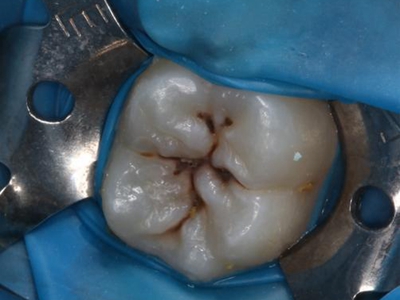

年轻恒牙龋好发于第一、二恒磨牙(牙合)面、邻面,上颌中切牙邻面,多为急性龋,龋坏进展快。平滑面的早期龋多为白垩色的斑片,点隙窝沟的早期龋多为浸墨状,表面粗糙。如果早期龋不及时治疗,可逐渐形成大而深的龋洞,易导致牙髓炎和根尖周炎。

年轻恒牙龋一般可进行充填治疗,对于早期的年轻恒磨牙,提倡采用微创的预防性树脂充填术、改良的预防性树脂充填术;深龋必要时考虑二次去腐修复。日常注意饮食,重视口腔卫生,考虑局部使用氟化物防龋,如含氟牙膏、含氟漱口水等,进行预防。对于年轻恒磨牙,可早期进行窝沟封闭,定期进行口腔检查。